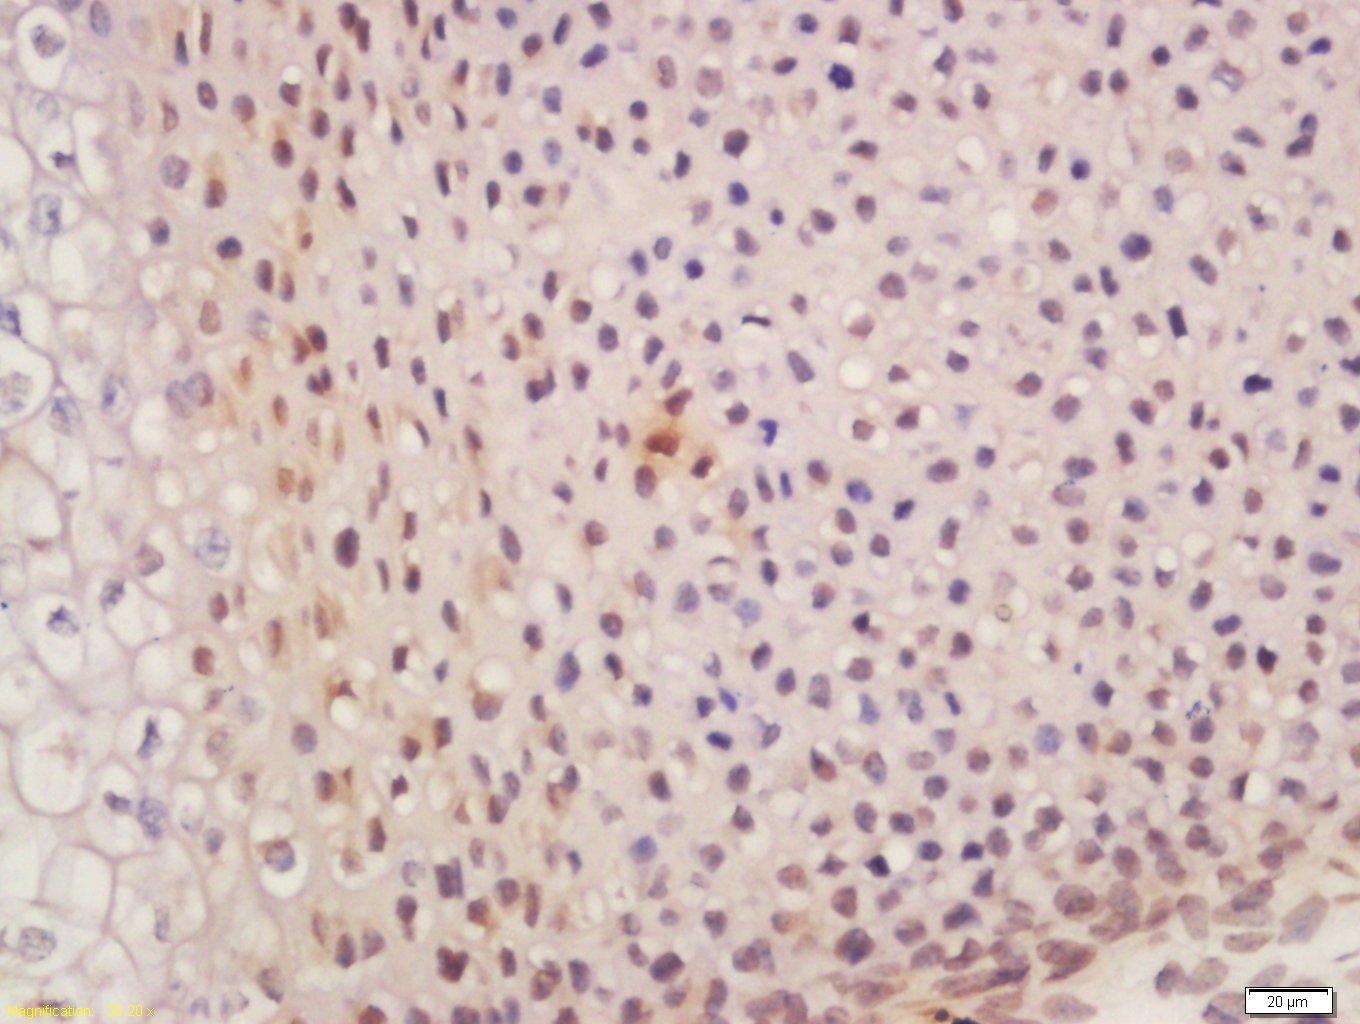

Tissue/cell: mouse embryo tissue; 4% Paraformaldehyde-fixed and paraffin-embedded; Antigen retrieval: citrate buffer ( 0.01M, pH 6.0 ), Boiling bathing for 15min; Block endogenous peroxidase by 3% Hydrogen peroxide for 30min; Blocking buffer (normal goat serum,C-0005) at 37℃ for 20 min; Incubation: Anti-SUFU Polyclonal Antibody, Unconjugated(bs-11209R) 1:200, overnight at 4°C, followed by conjugation to the secondary antibody(SP-0023) and DAB(C-0010) staining

Tissue/cell: rat brain tissue; 4% Paraformaldehyde-fixed and paraffin-embedded; Antigen retrieval: citrate buffer ( 0.01M, pH 6.0 ), Boiling bathing for 15min; Block endogenous peroxidase by 3% Hydrogen peroxide for 30min; Blocking buffer (normal goat serum,C-0005) at 37℃ for 20 min; Incubation: Anti-SUFU Polyclonal Antibody, Unconjugated(bs-11209R) 1:200, overnight at 4°C, followed by conjugation to the secondary antibody(SP-0023) and DAB(C-0010) staining